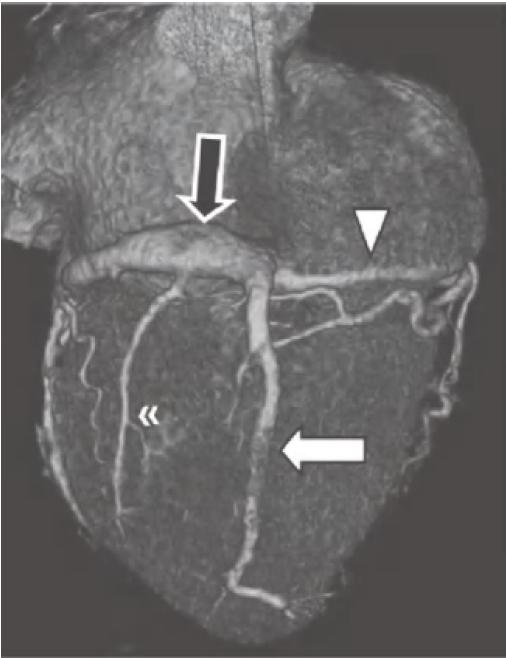

通常,RCA自右冠窦前方发出后在右房室间沟(RAVG)内向前然后向下走行,到达心脏的后方(图13-3及图13-4)。

图13-3 RCA(白箭)起自主动脉的前部,并沿RAVG(黑箭)走行。图中还可见位于前室间沟内(箭头)的LAD

AO.主动脉;PA.肺动脉;RA.右心房;RV.右心室;LV.左心室